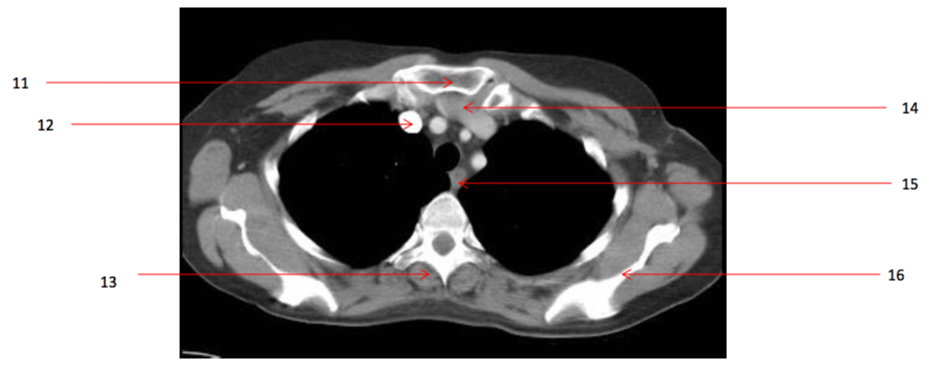

Number 13?

Number 16?

Number 14?

Number 11?

Number 12?